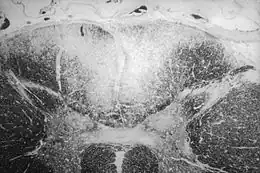

On désigne par le terme latin : Tabes dorsalis une dégénérescence des cordons postérieurs (ou colonnes dorsales) de la moelle spinale observée dans la neurosyphilis. Le mot latin tabes signifie « liquéfaction, dissolution, décomposition, atrophie. »